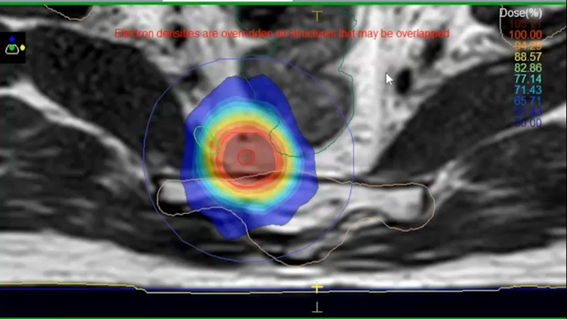

IMRTとは、コンピュータによる治療計画の最適化を行い、正常組織に投与されてしまう放射線の量を従来の外部照射よりも抑えることができ、かつ病変に集中的に放射線を投与することを可能にする照射です。当院では2011年よりIMRTを施行しており、主に前立腺がん、頭頚部がんに多く行っています。